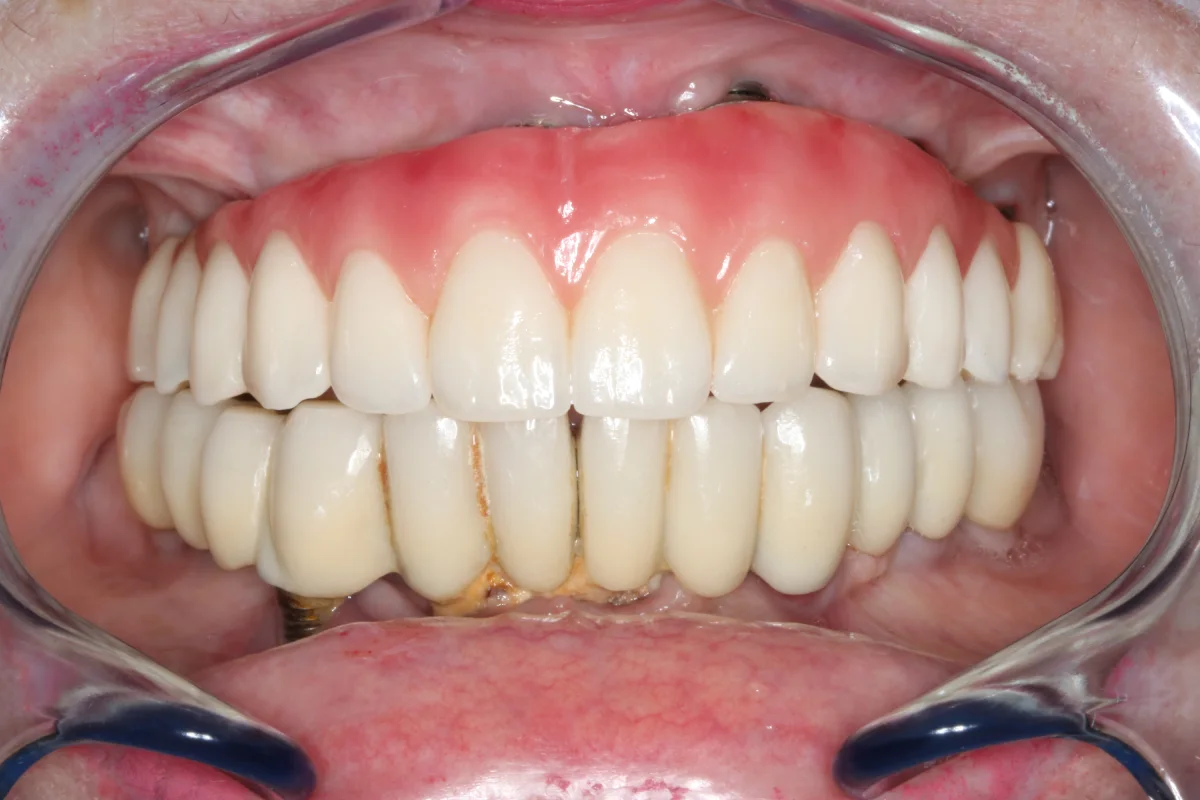

Siempre que el paciente reúna los requisitos clínicos adecuados, se irá con unas prótesis provisionales sobre los implantes que se colocarán en esa misma sesión.

Después Después